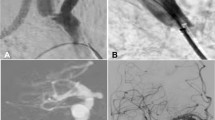

Two weeks after successful construction of animal models, angiography was performed (Fig. 1C–F) and covered stents were deployed to treat the lesion (Fig. 2A–H). In the first group with seven dogs of aneurysms and three dogs of arteriorvenous fistulas, a self-expandable covered stent was used in one CCA, and a balloon-expandable Willis stent on the other CCA in each dog. In the second group with three dogs of aneurysms and seven dogs of fistulas, a self-expandable covered stent was deployed in each CCA. A self-expandable bare stent was deployed in the subclavian artery in two groups. The components of the animal models (aneurysms or arteriovenous fistulas) were not significantly (P = 0.47) different in group one compared with group two. The stents deployed in each dog were not significantly (P = 0.52) different in group one compared with group two.

Deployment of covered stents to treat and gross specimen of experimental aneurysms and fistulas. (A, B). An aneurysm (arrow) made of venous pouches was shown on angiography (A), and deployment of a self-expandable covered stent eliminated the aneurysm (B). C&D. An arteriovenous fistula (arrow) between the external jugular vein and the carotid artery was shown (C), and deployment of the Willis stent immediately occluded the fistula (D, arrow). (E, F) Two aneurysms were made of venous pouches were shown after construction (E), and twenty days after deployment of a covered stent, the aneurysm (arrow) shrank significantly in vivo (F). (G, H) The aneurysm was excised (G), and non-completely-organized thrombi were presented within the aneurysm cavity after the aneurysm was cut open (H, arrow). (I) At 6 months, the aneurysm in vivo shrank significantly (arrow). (J) The orifice of a fistula between the external jugular vein and the carotid artery was covered by a thin layer of transparent substance (intima).